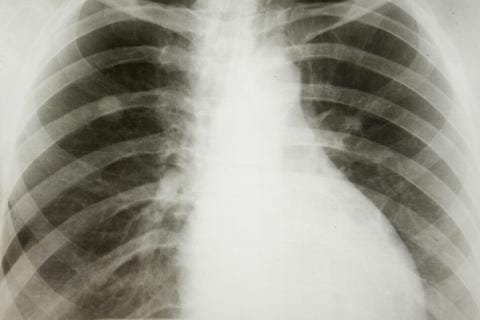

El cáncer del pulmón es una enfermedad que afecta de manera directa las células de los pulmones, provocando un crecimiento anómalo de las mismas, que poco a poco van minando y dañando los tejidos y el canal respiratorio.